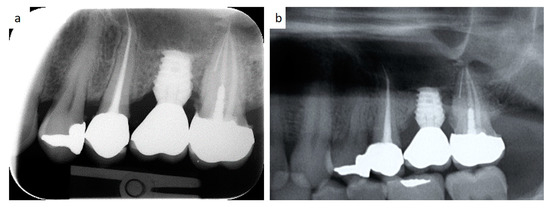

The surgical procedure is explained in detail in Figure 1a,b.

Figure 1. (a,b) Schematic description of the surgical technique allowing the formations of steps after drilling (a); as an example, the scheme is superimposed on a cone beam computed tomography (CBCT) of an atrophic posterior maxilla (b).